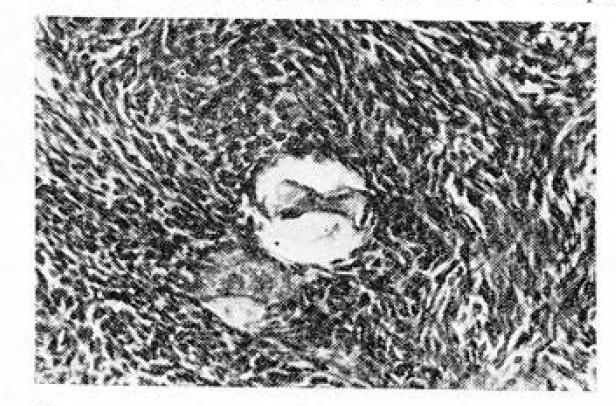

При изучении женских гонад привлекает внимание резкое обеднение фолликулярного апланата. Примордиальные фолликулы у больных в возрасте 30—39 лет отмечены в 12 наблюдениях из 20, в возрасте 40—49 лет — в 6 из 58. Во всех случаях примордиальные фолликулы были единичными и имели признаки глубокой дегенерации (рис.1). Малые зреющие фолликулы в 1-й возрастной группе обнаружены у 4 женщин, во 2-й — у 2. Большие зреющие фолликулы и граафовы пузырьки ни в одном случае нам не встретились.

Рис. 1. Плазмокоагуляция овоцита в яичнике больной раком матки. Окраска гематоксилин-эозином.Х 400.